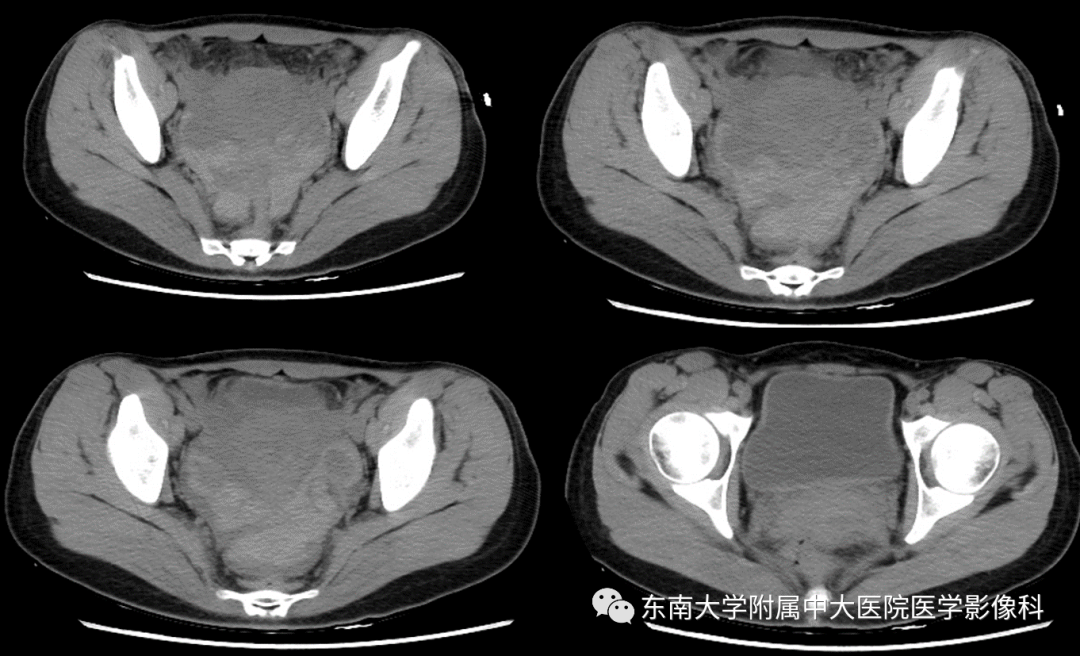

女,24岁,因“停经42天,下腹痛3小时”入院

影像学表现

病例结果:宫外孕破裂